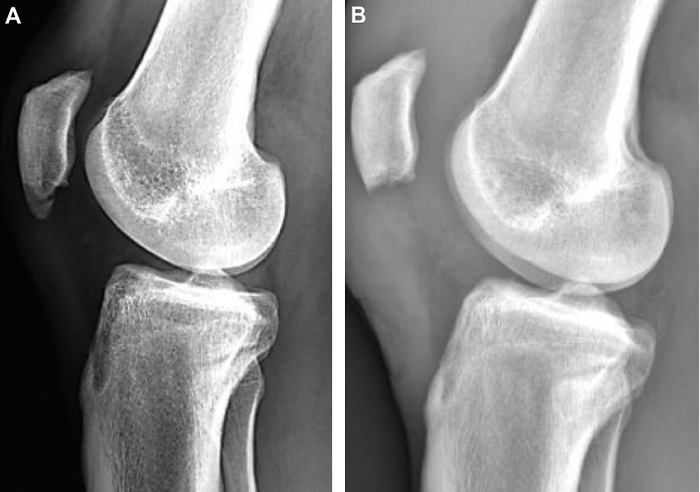

Sinding-Larsen-Johansson syndrome is another cause of knee pain in athletic children. While both disorders are caused by growth plate damage, Osgood-Schlatter occurs below the kneecap in the tibial tubercle. In contrast, Sinding-Larsen-Johansson occurs higher in the inferior pole of the patella.

Surgery is often not required because the bone is tougher than cartilage and less prone to irritation. The growth plate will eventually stop developing and fill with bone. If a person has bone fragments that have not healed or if there is an actual fracture, a doctor may recommend surgery in very rare circumstances. A surgeon, on the other hand, will not conduct surgery until the patient has stopped developing.